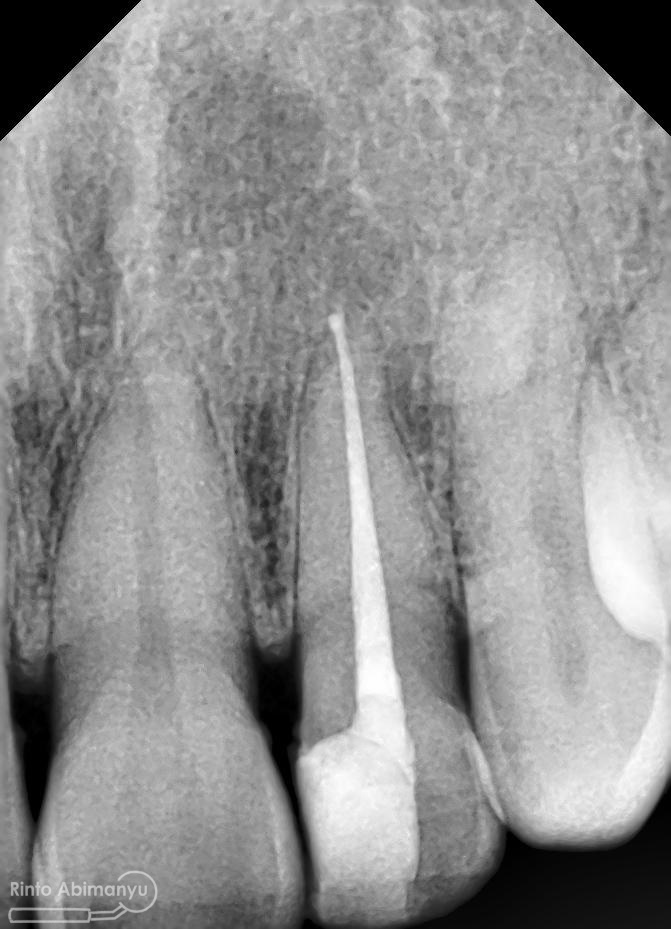

Setelah proses cleaning and shaping dilakukan trial gutta percha untuk melihat apakah kon utama yang akan kita gunakan pas dengan saluran akarnya…

Setelah melihat hasil ronsen trial guttap maka pengisian siap dilakukan… Untuk pengisian saluran akar saya memakai tehnik warm vertival condensation memakai alat Element Obturation Unit (SybronEndo) dan siler AH plus (Dentsply)…